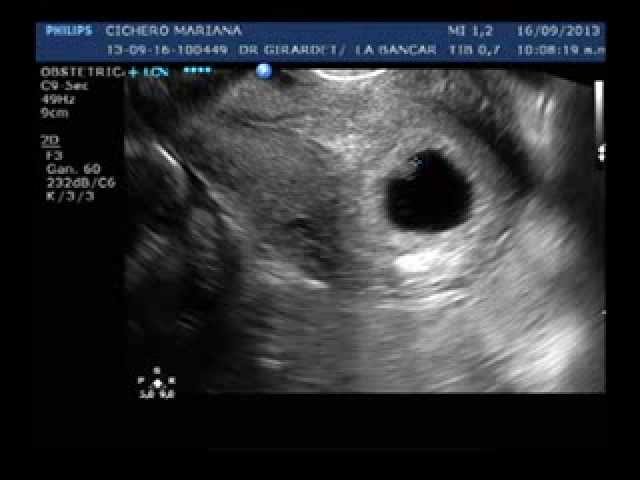

La ecografía transvaginal realizada a las 6 semanas de embarazo permite a los padres vislumbrar los inicios del desarrollo embrionario. ¿Qué revelaciones aguardan en esta etapa inicial? Acompáñanos en este recorrido por el asombroso universo de la gestación.

Uno de los momentos más emocionantes de una ecografía a las 6 semanas es la detección del latido cardíaco del embrión. ¿Cómo late el corazón en este punto crucial del embarazo? Descubre la maravilla de escuchar esos primeros latidos que dan inicio al pulso de la vida.

La ecografía revela detalles sorprendentes del embrión a las 6 semanas. Desde la formación de las extremidades hasta la presencia de la vesícula vitelina, cada descubrimiento es una pincelada en la obra maestra de la creación. ¿Qué secretos esconde el incipiente ser que se gesta en el útero materno?